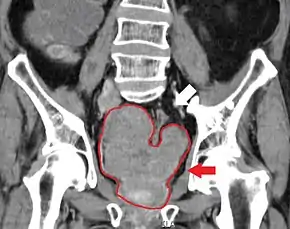

Staging

An important part of evaluating prostate cancer is determining the stage, or degree of spread. Knowing the stage helps define prognosis and is useful when selecting therapies. The most common system is the four-stage TNM system (abbreviated from tumor/nodes/metastases). Its components include the size of the tumor, the number of involved lymph nodes, and the presence of any other metastases.[94]

The most important distinction made by any staging system is whether the cancer is confined to the prostate. In the TNM system, clinical T1 and T2 cancers are found only in the prostate, while T3 and T4 cancers have metastasized. Several tests can be used to look for evidence of spread. Medical specialty professional organizations recommend against the use of PET scans, CT scans, or bone scans when a physician stages early prostate cancer with low risk for metastasis.[95] Those tests would be appropriate in cases such as when a CT scan evaluates spread within the pelvis, a bone scan looks for spread to the bones, and endorectal coil magnetic resonance imaging evaluates the prostatic capsule and the seminal vesicles. Bone scans should reveal osteoblastic appearance due to increased bone density in the areas of bone metastasis—the reverse of what is found in many other metastatic cancers.

In men with high-risk localised prostate cancer, staging with PSMA PET/CT may be appropriate to detect nodal or distant metastatic spread. In 2020, a randomised phase 3 trial compared Gallium-68 PSMA PET/CT to standard imaging (CT and bone scan). It reported superior accuracy of Gallium-68 PSMA-11 PET/CT (92% vs 65%), higher significant change in management (28% vs 15%), less equivocal/uncertain imaging findings (7% vs 23%) and lower radiation exposure (10 msV vs 19 mSv). The study concluded that PSMA PET/CT is a suitable replacement for conventional imaging.[96]

Sclerosis of the bones of the thoracic spine due to prostate cancer metastases (CT image)

Sclerosis of the bones of the thoracic spine due to prostate cancer metastases (CT image) Sclerosis of the bones of the thoracic spine due to prostate cancer metastases (CT image)

Sclerosis of the bones of the thoracic spine due to prostate cancer metastases (CT image) Sclerosis of the bones of the pelvis due to prostate cancer metastases

Sclerosis of the bones of the pelvis due to prostate cancer metastases